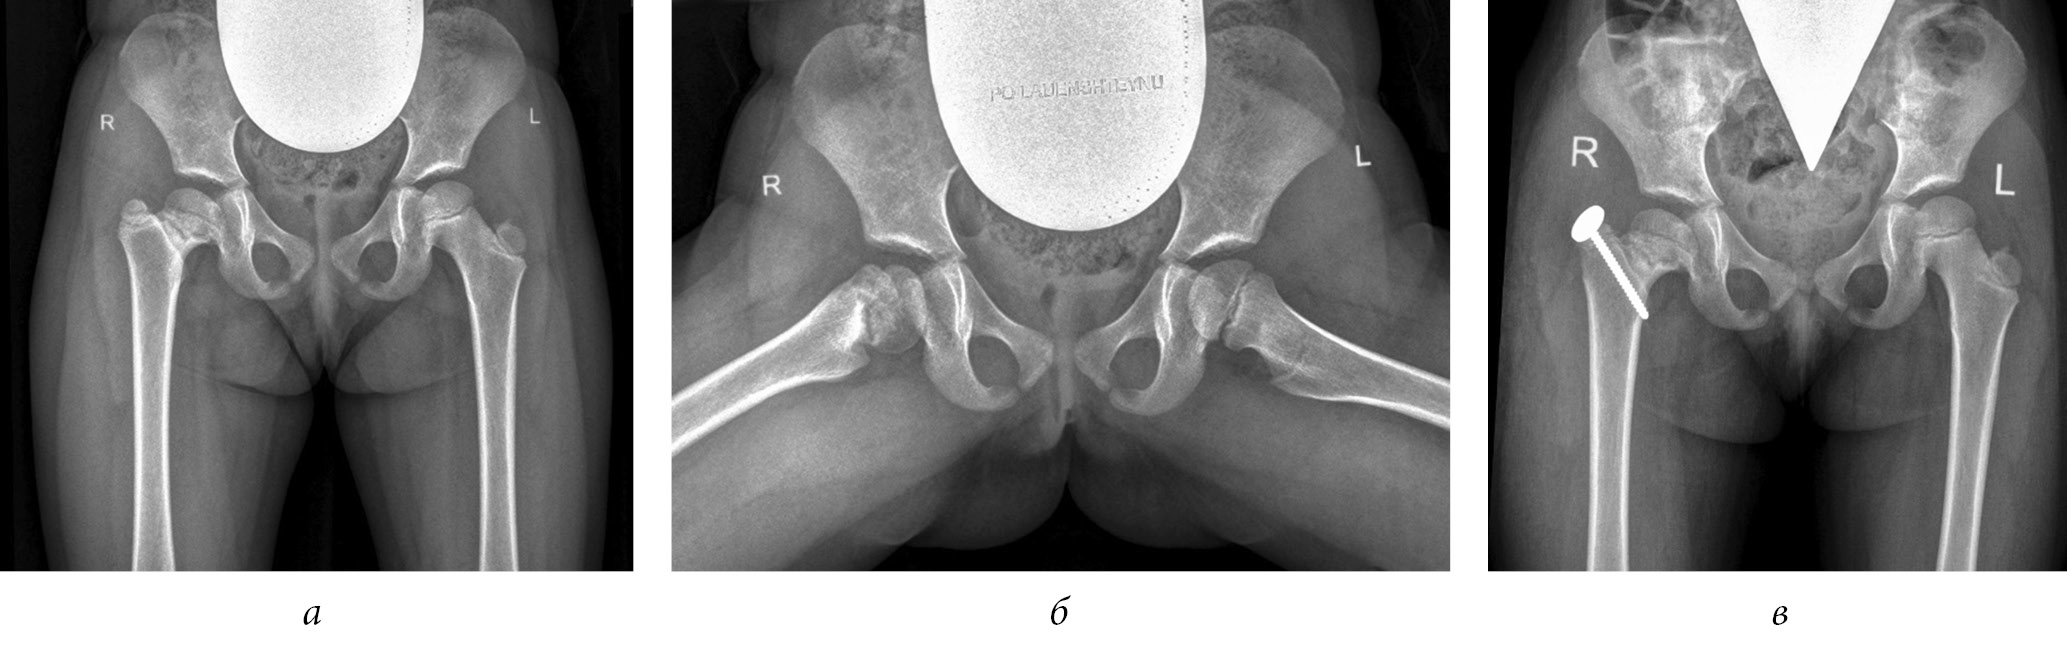

To exclude displacement of the greater trochanter, adherence to bed rest, or use of ambulation support in the postoperative period, before the destruction of the growth zone, the greater trochanter was fixed to the femur using an eight-shaped plate with screws or a cortical screw with a washer. The eight-shaped plate was installed from the lateral surface of the hip, and the cortical screw was inserted from the superior lateral parts of the greater trochanter toward the lesser trochanter parallel to the intertrochanteric line of the femur (Figs. 1, 2) [19].

Fig. 2. Radiographs of patient G (4 years old) diagnosed with complications of septic arthritis of the hip joint, emerging high position of the greater trochanter on the right, and multiplanar deformity of the femoral neck with eccentric growth of the epiphysis posteriorly: a, b, before surgery; c, immediately after trochanteric epiphysiodesis on the right